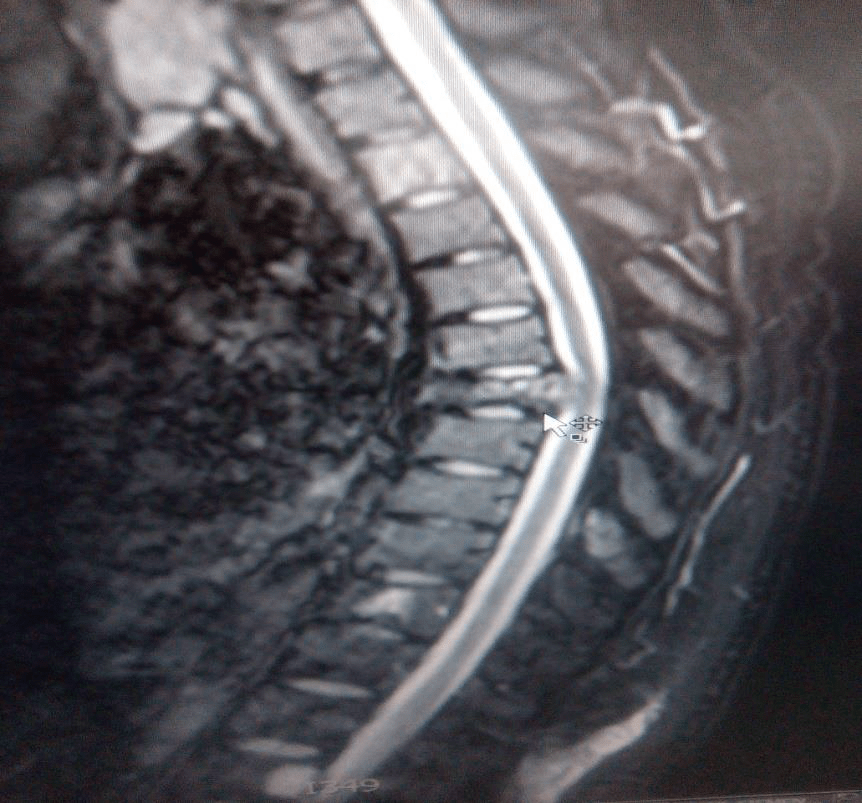

The tests were repeated for the patient again, general and comprehensive blood tests were performed and all agreed to a high levels of adrenal hormones in blood , radiographic images were also done in addition to magnetic resonance images throughout the body, the result of the tests and imaging was for the brain CT scan showed that there was no focal brain lesion and it was a metastatic spread test only, and no shift of midline structure and normal ventricular system, as the lumber spine CT showed that the findings were evidence of multiple bony lytic lesions seen in the lumber spine and sacral bone and no evidence of disc herniation or nerve root compression as showed in figure (7 ), this all tells that all back pains suffered by the patient were due to the presence of the tumor only .

The pelvic MRI showed that there were multiple hyper intense signals seen in the left ischium, that suggested bone metastasis while the abdominal MRI showed that there were a 6.75.3 cm right a adrenal mass lesion which appears isointense with thick wall moreover the neck Ultra sound showed a (97*11 ) mm nodule in the lift lobe with spots of calcification in the thyroid gland enlarged and indicating thyroiditis, after all of those critical signs shown through the previous medical scans , PET-CT scan was advised to insure the presence and the location of the primary lesions and the metasticitc spread , and after undergoing a PET-Ct scan the result showed a hypermetabolic and mostly malignant right adrenal mass with bone metastasis .

The first treatment was done and a pre ablation scan was performed and showed a wide spread metastases. Six months after this image the patient was imaged again after the repetition of the previous Lu177DOTATE therapy as a second cycle treatment. The next day of the injection and here a great difference shows in the image as a great benefit and good remission in the

metastatic malignancy due to the use of Lu177DOTATE therapy which did not happen with any other treatment technique used with the patient specially the chemotherapy used before.

Figure17: Great PR appears as a result of the 177Lutitum DOTATAT radionuclide therapy after 6 months of the first cycle (16- Jordanian medical services, PACS system and database store center).